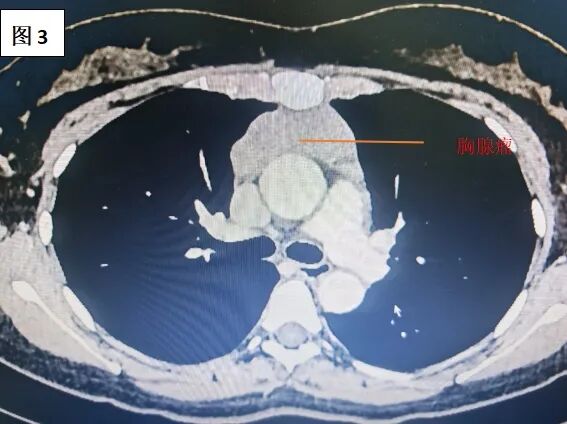

胸部强化CT显示,胸腺瘤体积大,已侵犯左无名静脉并累及上腔静脉,血管管腔严重受压。如果不及时手术,肿瘤继续侵犯更多脏器,可能引发上腔静脉综合征,导致头面部水肿、呼吸困难,甚至危及生命。